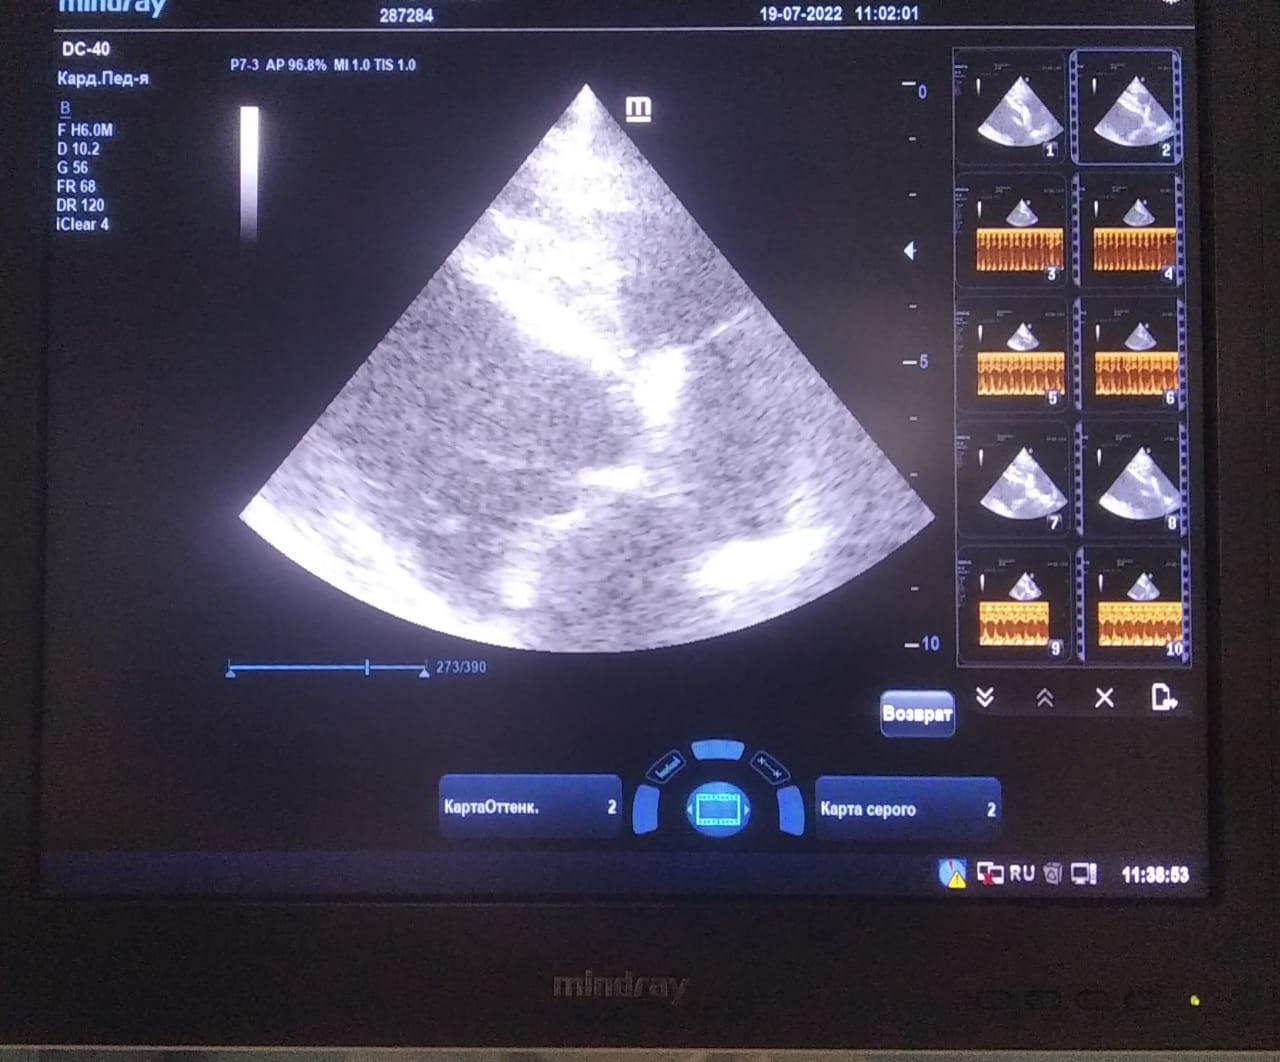

Анализы Арчи. Сердца и легких

Вложения

IMG-20220719-WA0100.jpg

IMG-20220719-WA0102.jpg

IMG-20220719-WA0104.jpg

IMG-20220719-WA0103.jpg

IMG-20220719-WA0105.jpg

Продолжение.